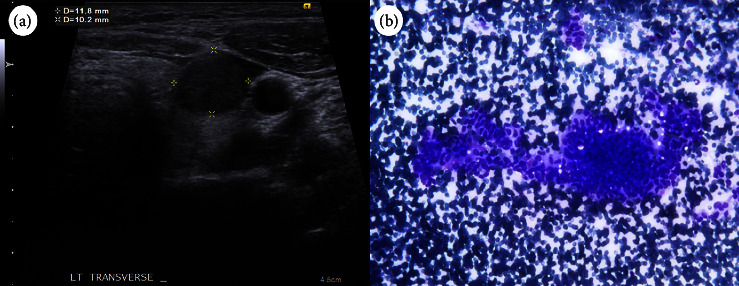

Results: A 31-year-old woman was found to have a thyroid nodule at the left lobe measuring 11.8 × 10.2 × 12.4 mm. Ultrasonography indicated a hypoechoic, solid nodule with regular margins. Cytology revealed a papillary structure of tall cells, leading to a PTC diagnosis. Nevertheless, the genetic analysis failed to detect mutations such as BRAF V600E, NRAS Q61R, NRAS Q61K, HRAS Q61R, or HRAS Q61K mutation or the fusion of CCDC6-RET, NCOA4-RET, PAX8-PPARG, ETV6-NTRK3, TPM3-NTRK1, IRF2BP2-NTRK1, or SQSTM1-NTRK1 in the aspirated follicular cells. The patient subsequently underwent total thyroidectomy with central lymph node dissection. Pathological examination revealed a cribriform pattern of spindle-shaped cells with morular areas. Immunohistochemical staining showed positive results for β-catenin and TTF-1, except in the morular regions, and negative results for PAX8, thyroglobulin, and BRAF (clone VE1). The diagnosis was confirmed to be cribriform morular thyroid carcinoma.